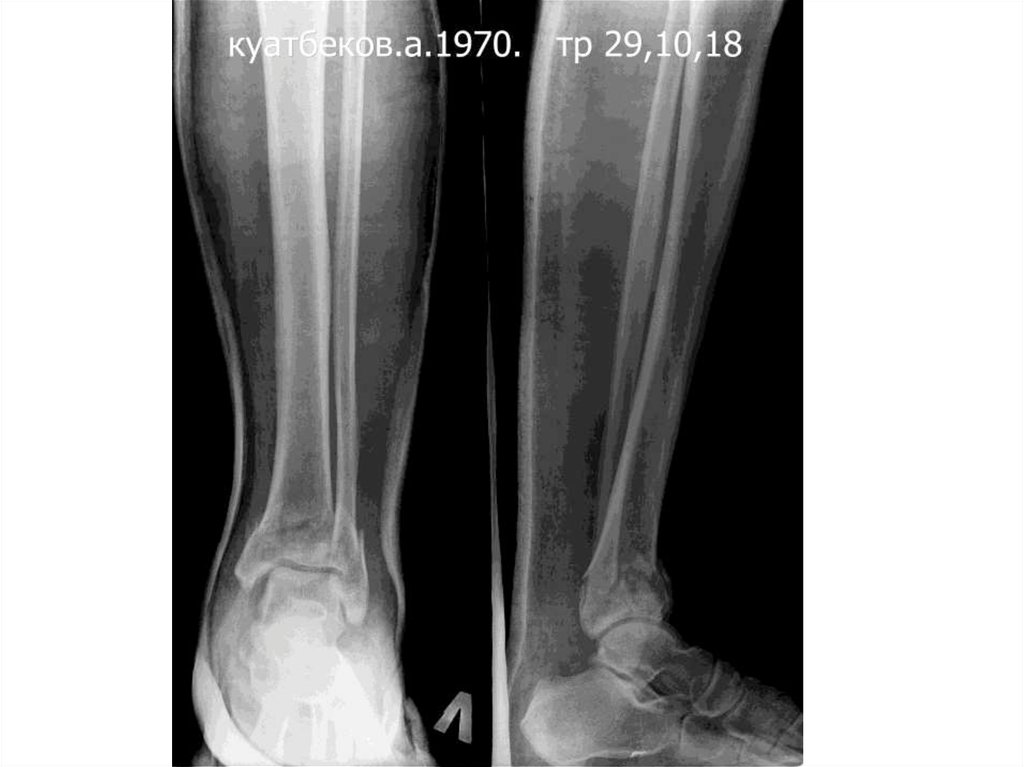

КУАТБЕКОВ АСКАР 28.12.1970

(37жас)

• Сол асықты жіліктің төменгі 1/3 сынуы,

ығысумен. Шыбық сүйектің жоғарғы 1/3

бөлігінің ығысумен сынуы. Сол балтырдың

жоғарғы 1/3 жыртылған жарасы.